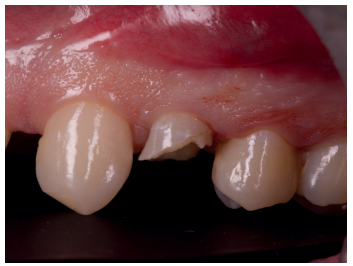

Una vez se hubo posicionado el diente 2 mm supragingival, se procedió a la ferulización con alambre de acero a los dientes adyacentes (Figuras 3 y 4) y la eliminación de cualquier tipo de oclusión, utilizando topes oclusales en los segundos molares inferiores. La ferulización se mantuvo durante dos semanas, coincidiendo con el momento de la endodoncia (Figura 5). El paciente fue citado para las revisiones periódicas y posteriormente para la rehabilitación del diente, una vez hubieron concurrido 6 semanas desde la extrusión, en las que se haya obtenido una cicatrización de los tejidos de soporte supracrestales10. En este momento, tras comprobar signos clínicos, periodontales y radiográficos saludables, se citó al paciente para el tallado y la confección mediante flujo digital (Cerec® System) de una endocorona de disilicato de litio (e.max®, Ivoclar Vivadent). El acondicionamiento de la corona se realizó con ácido fluorhídrico y silano, y para la cementación se utilizó cemento de resina (Calibra®, Dentsply Sirona).

adyacentes, tras la extrusión quirúrgica.